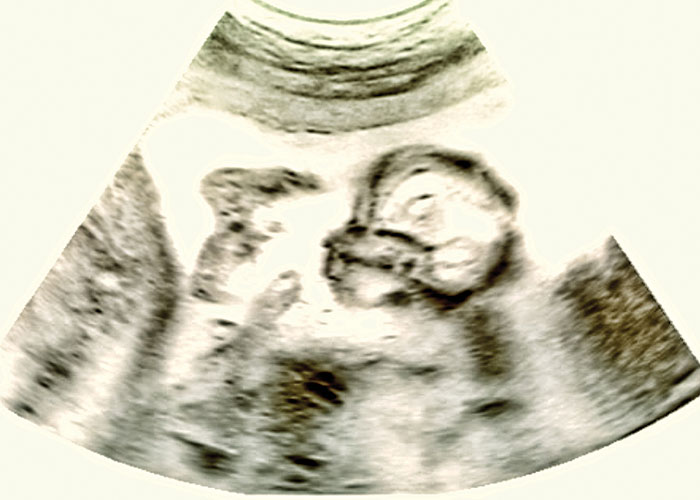

En este sentido, una de las experiencias de la universidad que llamó la atención de los medios fue un estudio de septiembre de 2020 publicado en Scientific Reports. El estudio desacredita los esfuerzos de los investigadores por desarrollar “ratones humanizados” mediante el trasplante de partes del cuerpo fetal a roedores. El material necesario para crear injertos de piel en roedores se habría obtenido de abortos de bebés de entre 18 y 20 semanas.